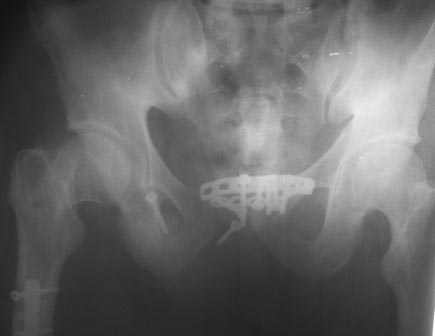

тактике лечения? Снимки: 1. При поступлении. 2. Послеоперационный. 3. от

05.03.2013г.

Имя     : 1.jpg

Тип     : image/jpeg

Размер  : 25688 байтов

Описание: отсутствует

Url     : http://weborto.net:8080/pipermail/ortho/attachments/20130306/d918acc1/attachment-0006.jpg